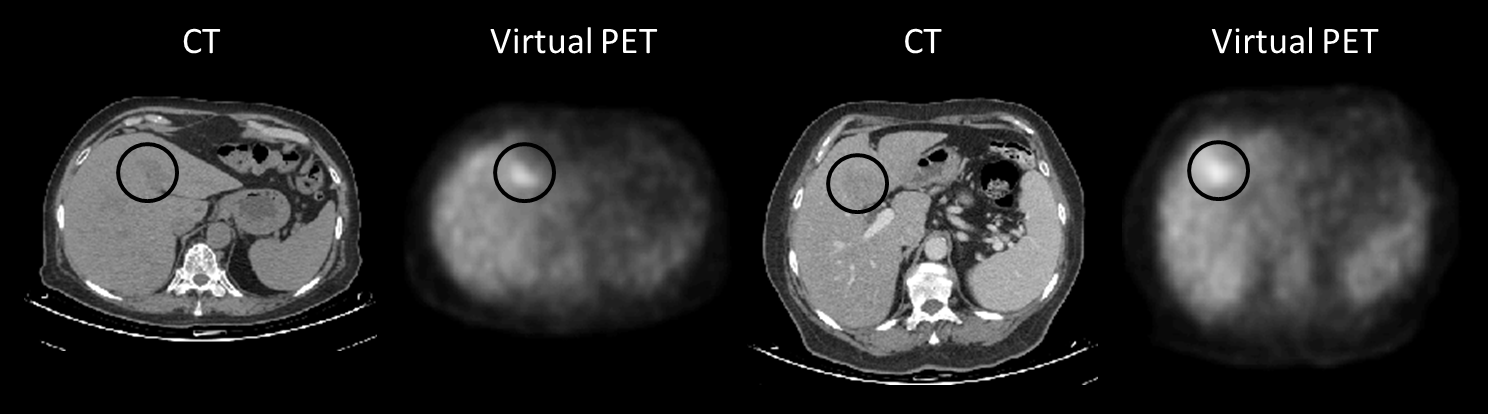

Fig. 4 shows sample results obtained using the FCN, and FCN blended with the conditional GAN, compared to the real PET scan. False positive examples are shown in Fig. 5. In these cases, the FCN mistranslated hypodense regions in the liver to high SUV values.

Refer to caption

Figure 5: False positive examples are marked with a black circle.